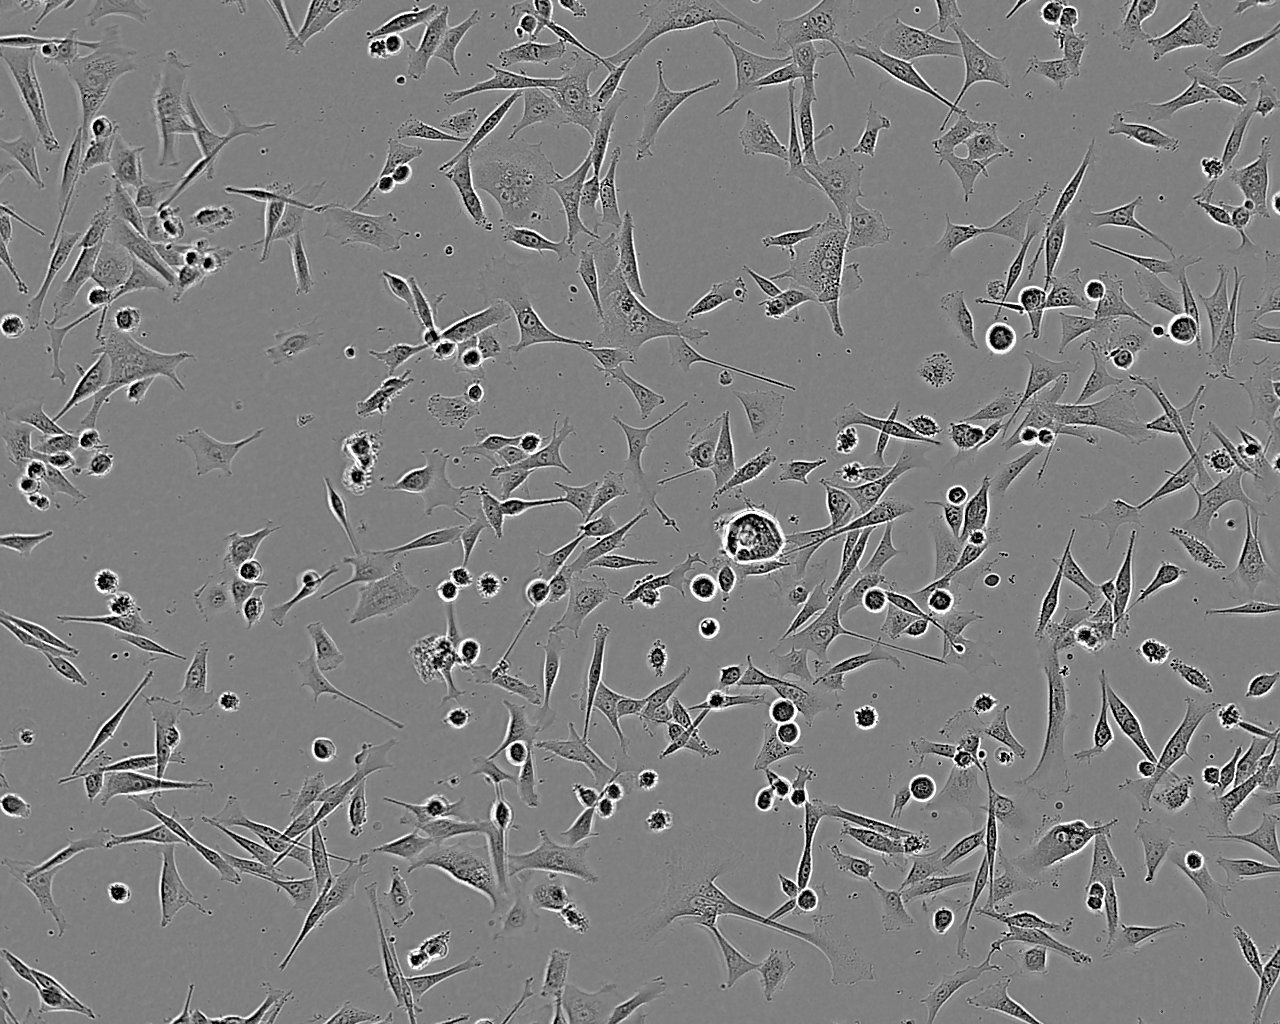

Cell Type

Fibroblastic

Growth Mode

Adherent

Split sub-confluent cultures (70-80%) seed new cultures at 2-4x10,000 cells/cm² using 0.05% trypsin or trypsin/EDTA; 5% CO₂; 37°C. Saturation density 15 x 10⁴cells/cm².